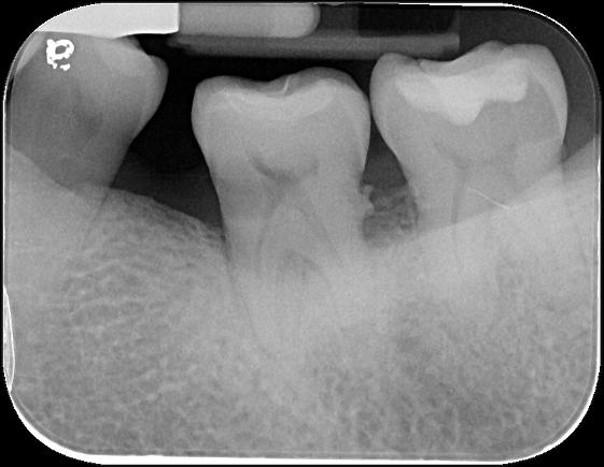

治療前,再次蛀牙,牙齒排列不整

蛀牙已至牙髓

#37-顯微根管治療